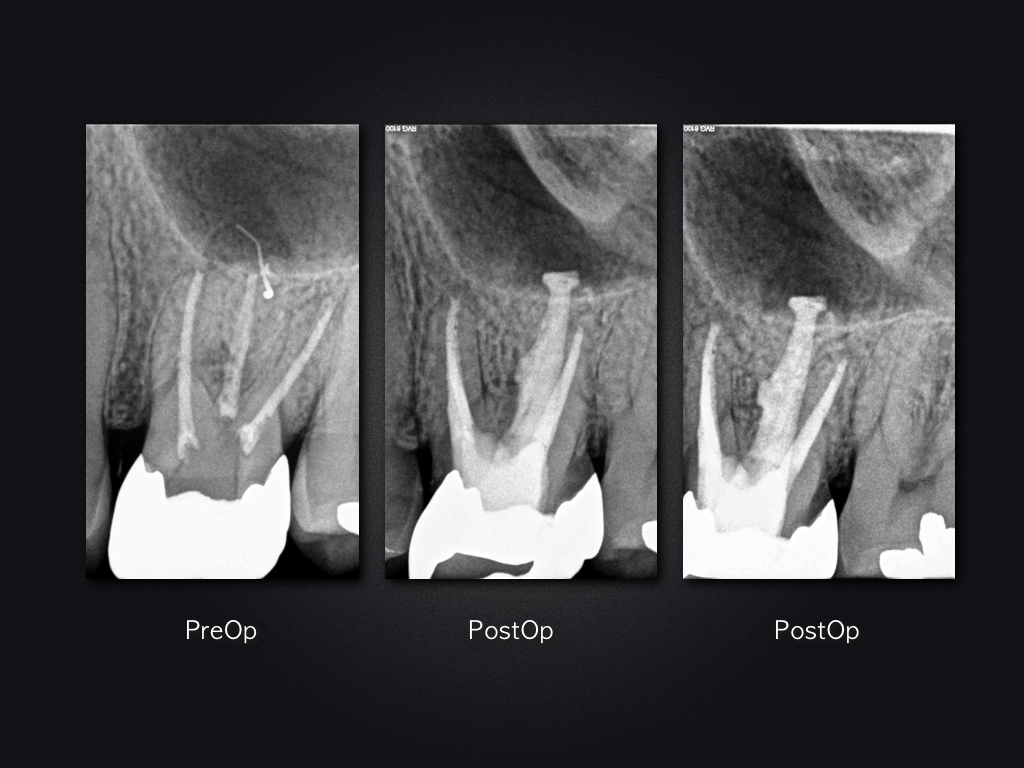

26D.016

2D vs. 3D (XXV)